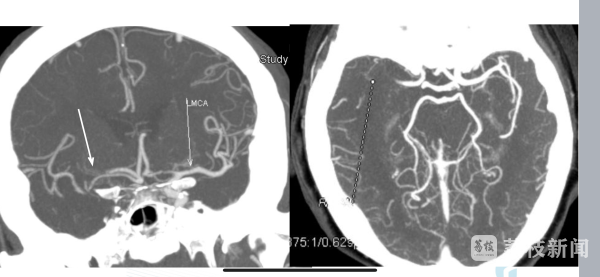

为加快病人救治,江苏省人民医院还在急诊部设立用于取栓的复合手术室。过去7年间,医院已通过绿色通道成功救治超千名脑卒中患者。脑卒中急救有"黄金三小时",如果您身边有人发生脑卒中,应该第一时间做出反应,请牢记"120"口诀。

江苏省人民医院介入科主任、卒中中心执行主任施海彬说:“‘1’就是一张脸,嘴歪了,‘2’就是两只胳膊只能抬起一边,另外一边抬不起来了,‘0’是聆听声音,话讲不起来了。所以只要三个问题中间任何一个出现,或怀疑到这个问题,赶紧拨打120。”